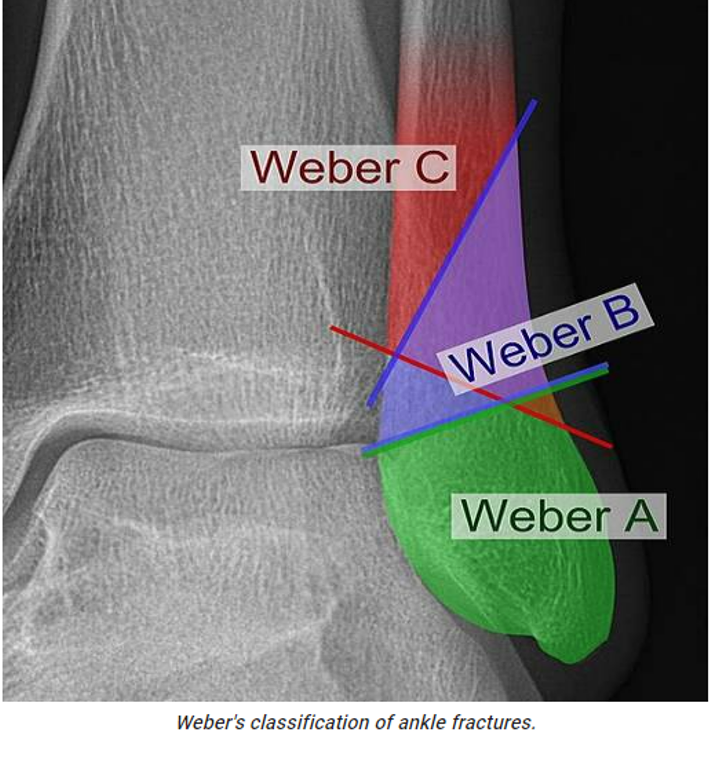

Weber classification –> ankle fractures

• Type A: lateral malleolar fracture below level of syndesmosis, stable fracture, deltoid ligament intact

• Type B: lateral malleolar fracture at level of syndesmosis, may be stable or unstable, deltoid ligament may be torn

• Type C: lateral malleolar fracture above syndesmosis, unstable injury, deltoid ligament injury present, open